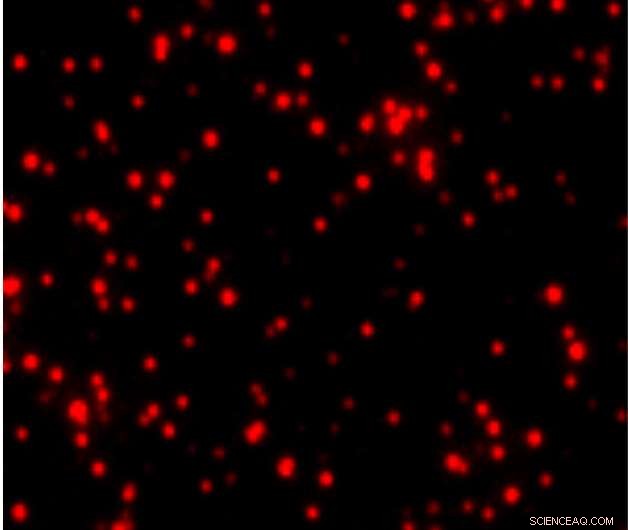

This SMAC image shows mutant p53 proteins in the blood of an ovarian cancer patient. Individual clusters of p53 molecules are represented by red spots. Credit: Shih-Chin Wang

Wang and colleagues call their new approach Single-Molecule Augmented Capture (SMAC). They used this new technique to detect molecules commonly screened for in standard blood tests, like prostate-specific antigen. And they were also able to detect rare intracellular proteins, secreted proteins and membrane proteins, including the cancer-associated proteins mutant p53, anti-p53 autoantibodies and programmed death-ligand 1 (PD-L1).

Mutant p53 is a well-known tumor-specific nuclear protein and has never before been detected in the blood, likely because current tests cannot detect its extremely low blood concentrations. Wang and colleagues found mutant p53 or anti-p53 autoantibodies in samples from patients with ovarian cancer, but not in patients without cancer. PD-L1 is also found on the surface of some cancer cells and has recently been effectively targeted with immunotherapy to combat cancer. Knowing whether or not a patient's tumor expresses PD-L1 is a crucial first step in this treatment—and SMAC may be able to identify cancers that have PD-L1 at low levels that are undetectable by standard blood tests.